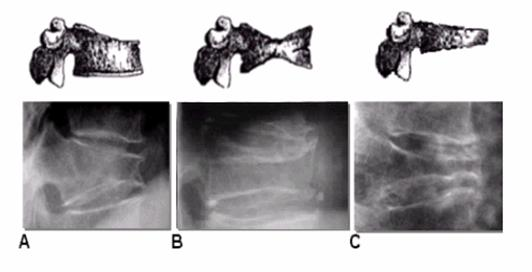

Types of fractures: to confirm the diagnosis, the radiograph must clearly identify the contours of the vertebral bodies to evaluate the decrease in any of the vertebral heights or break in the cortical edge and classify as wedge, biconcave or crushing Figure 5.

Biconcave fractures are produced by collapse of the central portion of the vertebral body Figure 6, and crushing is when the entire vertebral body has collapsed Figure 7.

Figure 6 Numbers 3 and 4 show biconcave fractures with collapse of the central region

Figure 7 C shows vertebral collapse, B biconcave and A wedge-shaped.